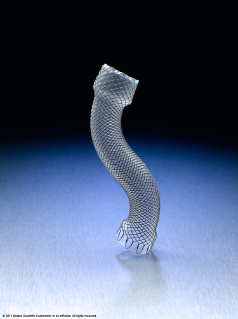

Imágenes del Stent esofágico

Examine las imágenes que desea usar en las presentaciones.